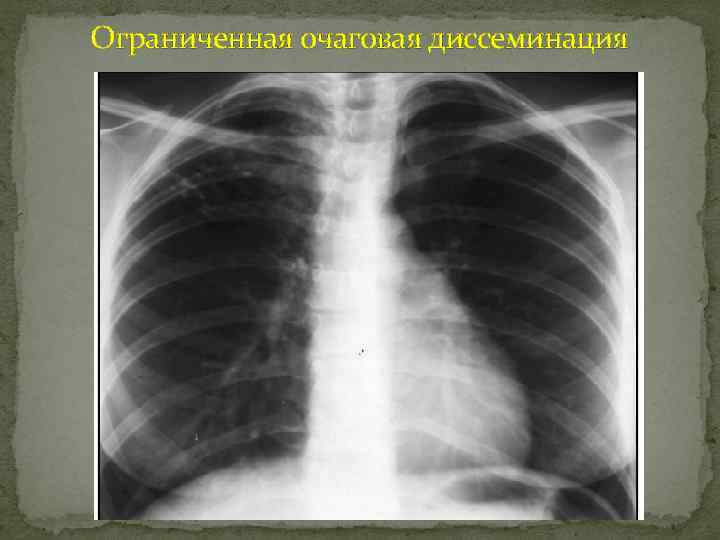

Ограниченная очаговая диссеминация (очаговый Туберкулез) Очаговые тени

Ограниченные очаговые диссеминации Очаги и ограниченные очаговые диссеминации - округлые, полигональные или неправильной формы тени размером до 12 мм, анатомической основой которых является долька легкого. Несколько очагов, расположенных рядом, обозначают как группу очагов. Ограниченные диссеминации - это определяемые на рентгенограмме множественные очаги, локализующиеся в пределах не более двух сегментов. Наиболее часто этим синдромом отображаются очаговый туберкулез, периферический рак, метастазы, дольковые ателектазы, аспирационные пневмонии. 1.

Ограниченная очаговая диссеминация